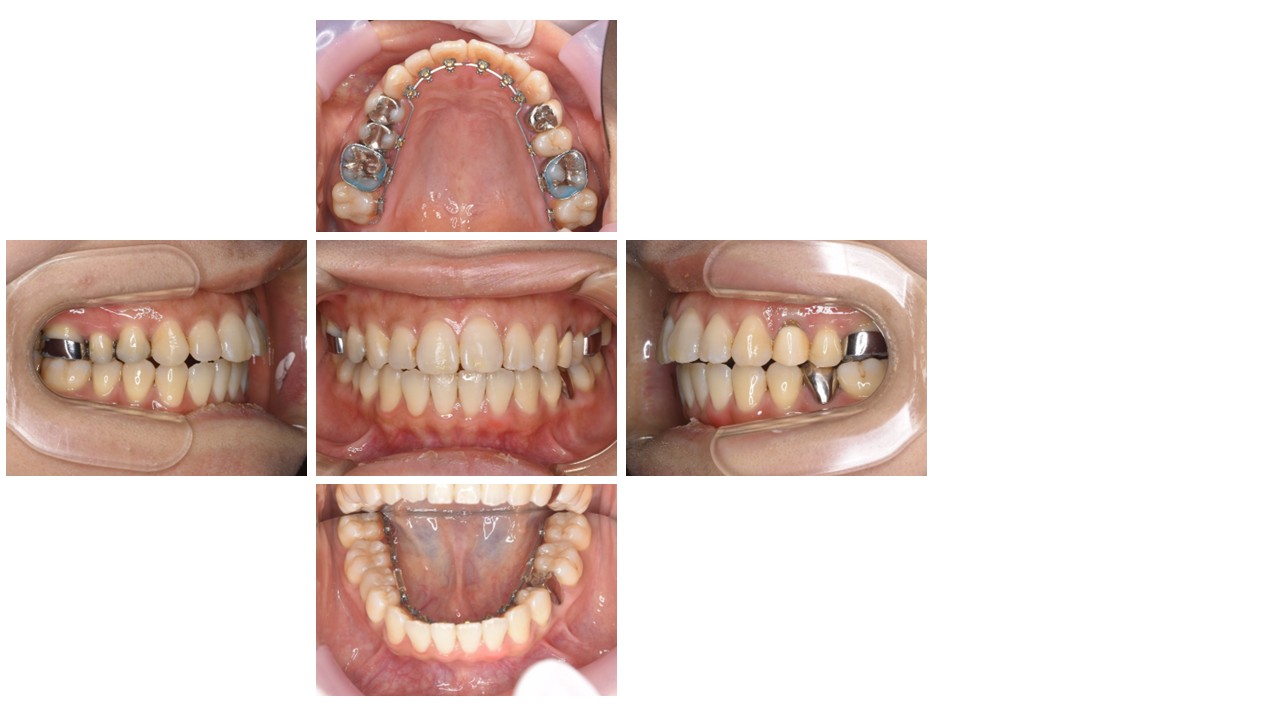

矯正治療/上顎前突(上の歯がでている)開口(前歯が咬めない)

20代女性

主訴:前歯が出ている 口元がでている

診断・症状:上顎前突 前歯部開口

抜歯部位:非抜歯

装置:リンガル(舌側矯正) 矯正用アンカースクリュー使用

治療期間:1年10か月

治療費:1,287,000円(10%税込み) *処置料・再診料・保定料を含む

治療後